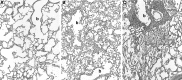

Much of the progress in improved neonatal care, particularly management of underdeveloped preterm lungs, has been aided by investigations of multiple animal models, including the neonatal baboon (Papio species). In this article we highlight how the preterm baboon model at both 140 and 125 days gestation (term equivalent 185 days) has advanced our understanding and management of the immature human infant with neonatal lung disease. Not only is the 125-day baboon model extremely relevant to the condition of bronchopulmonary dysplasia but there are also critical neurodevelopmental and other end-organ pathological features associated with this model not fully discussed in this limited forum. We also describe efforts to incorporate perinatal infection into these preterm models, both fetal and neonatal, and particularly associated with Ureaplasma/Mycoplasma organisms. Efforts to rekindle the preterm primate model for future evaluations of therapies such as stem cell replacement, early lung recruitment interventions coupled with noninvasive surfactant and high-frequency nasal ventilation, and surfactant therapy coupled with antioxidant or anti-inflammatory medications, to name a few, should be undertaken.